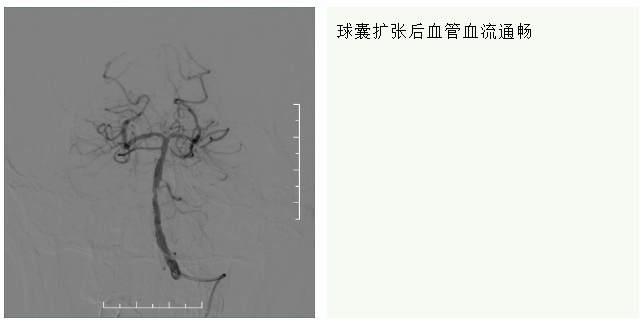

手术由我院神经外科主任樊永忠和神经内科副主任医师欧阳和中进行。术中,穿刺针由右股动脉成功入路,在基底动脉头端抽吸出3块暗紫色血栓,通过造影后见后循环恢复血流,但基底动脉起始部重度狭窄。观察10分钟后,通过造影,发现基底动脉再次闭塞,再次抽吸后血流恢复,但仍可见重度狭窄。为了解决这个问题,术中进行了基底动脉球囊扩张成形术,球囊扩张血管后,狭窄解除,造影可见血流通畅,手术成功完成。